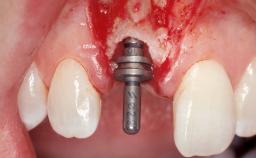

Late Flapless Placement of an Implant in a Maxillary Left Central Incisor Site

A 39-year-old male patient presented with a chief complaint of discomfort and gingival discoloration around his maxillary left central incisor. He was in good general health and was a non-smoker. His past dental history was significant because of the traumatic fracture of tooth 21 in a sporting accident at age 13. Initial dental treatment included endodontic therapy and a full-coverage restoration. The patient became symptomatic 5 years later, when structural failure of the tooth resulted in the dislodgment of the crown. Endodontic retreatment, apical surgery, and post-and-core restoration were performed.

Placement Protocol Early or late implant placement

Bone Volume Deficient horizontally, requiring prior grafting